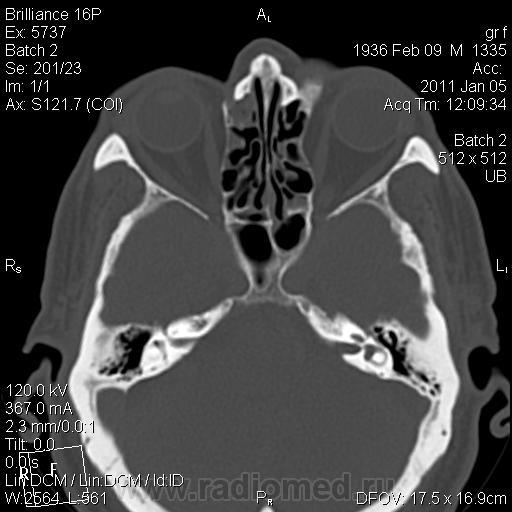

Толстые костные стенки пазухи, внутренние контуры с выступами и словно волнообразные, но ровные, четкие. 2х2,5 см.С более нежной (хрящ?) структурой к центру. А в самом центре 55 HU 1-сантиметровый полип? Я просто не знаю, как трактовать...

Точно без деструкции. А структура - костная. С переходом к центру в хрящ. А каким местом полип затесался - вот и не знаю... Если это полип.

У меня два варианта: фиброзная дисплазия и гиперостоз в результате хронического воспалительного процесса в пазухе. А нельзя ли спросить у пациента как давно эта шишка появилась?

Вторичный гиперостоз тоже вариант, но при нём должны быть более выраженные склеротические изменения в купе с утолщением.

Они более толстые и более нежные, аморфные, что ли)).

Коль "аморфные", тогда больше за фиброзную дисплазию.

Я больше склоняюсь в пользу мукоцеле пазухи с реактивным гиперостозом. Фиброзная дисплазия все же редко бывает настолько локальной.

Мукоцеле? Да где же оно? Для мукоцеле все же более характерна атрофия от давления.

Есть есть выбухание пазухи кнаружи, значит есть давление, а значит - и атрофия от нее;) А гиперостоз - это другой процесс))